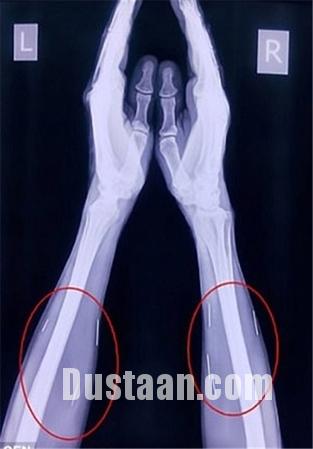

پزشکان با مراجعه مردی جوان به بیمارستان که عنوان داشت در ناحیه گلو و کف پایش احساس درد دارد، اقدام به عکسبرداری از وی کردند، انها در کمال تعجب مشاهده کردند که بیش از ۷۵ سوزن در گلو و دیگر بخش های بدن او فرو رفته است!

«بادریلال مینا» که از اهالی ایالت راجستان است، از وجود این سوزن ها اظهار بی اطلاعی می کند! اما حقیقت چیز دیگریست چرا که فرو رفتن این سوزن ها در بدن وی قطعا بدون درد نبوده و وی از وجود سوزن ها مطلع بوده است.